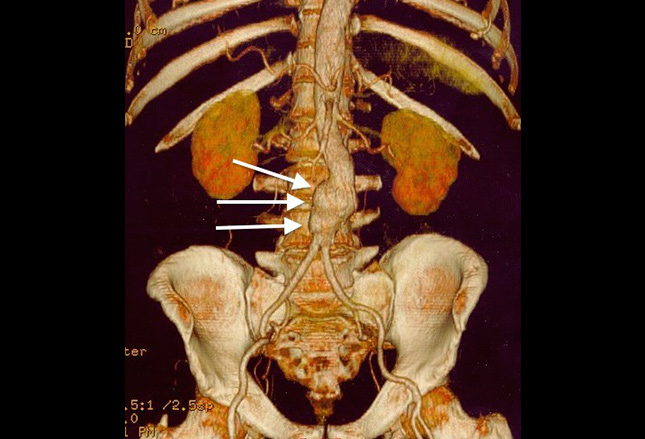

CT扫描对比揭示了无症状的老年男性中的腹主动脉瘤。动脉瘤壁上和远端主动脉(a)有钙化的动脉粥样硬化斑块。

因为腹主动脉瘤的表现可能是多变的,并且风险随着年龄增加,从怀疑腹主动脉瘤的稳定老年患者中获得成像研究是非常必要的。床旁超声对腹主动脉瘤评估具有敏感性和特异性,可改善诊断时间;然而,这种方式并不是总能发现腹膜后破裂。CT血管造影

(CTA)可以用来评估稳定患者中的腹主动脉瘤破裂。